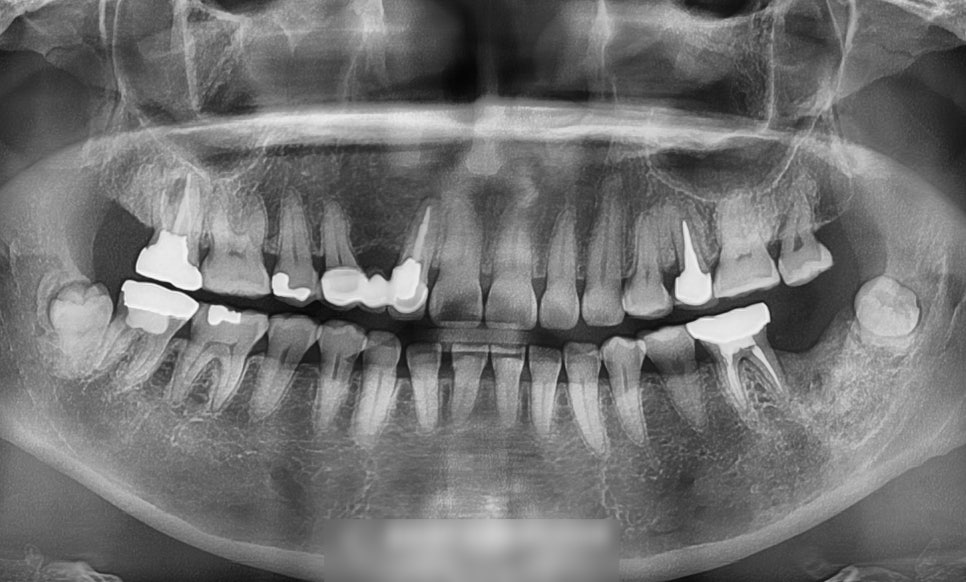

전체 파노라마 사진을 통해 확인해볼 수 있습니다.

다행히 크게 벌어짐이 있지 않으며

오밀조밀 잘 붙어있습니다.

아래 앞니 쪽만 개선이 필요합니다.

하악 전치부의 간격에 의하여

Space가 눈에 띄게 도드라집니다.

특히 41번과 42번에서의 간격이

넓은 편이었기에 진행되는 과정을 파악해

기간을 결정해야 될 것으로 사료됩니다.